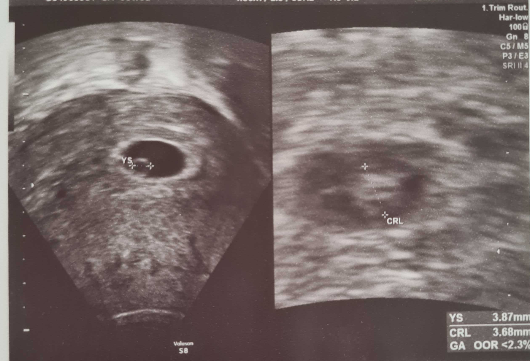

まだ3.68mmですが

頑張って動いていると思うとびっくり!😮!

小さな小さな胎嚢がしっかりと子宮内で確認できました😊💕